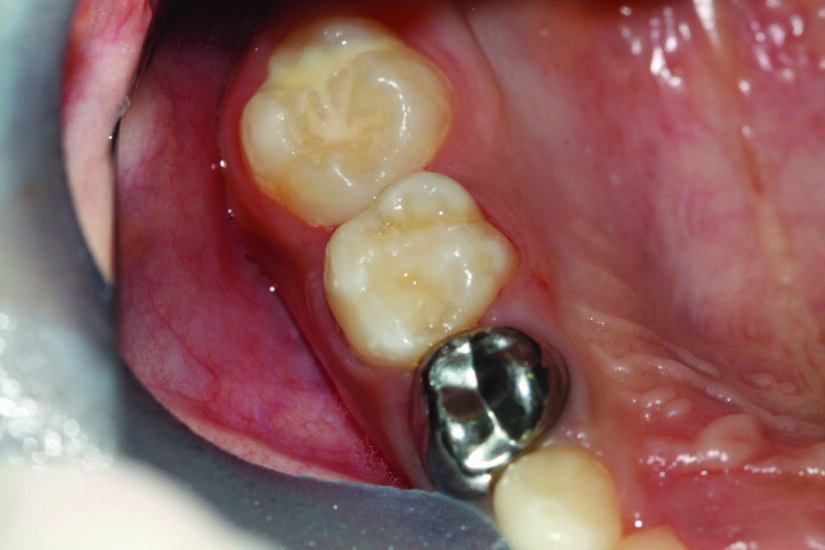

Figure 2: A periapical radiograph showing ectopically erupted upper right first permanent molar.

Treatment depends on how severe the impaction appears clinically and radiographically. For mildly impacted first permanent molars, where little of the tooth is impacted under the primary second molar, elastic or metal orthodontic separators can be placed to wedge the permanent first molar distally4, Figure 3. For more severe impactions, distal tipping of the permanent molar is required. Tipping action can be accomplished with brass wires, removable appliances using springs, fixed appliances such as sectional wires with open coil springs, Figure 4, sling shot-type appliance3, Figure 5, a Halterman appliance5, Figure 6, or surgical uprighting6.